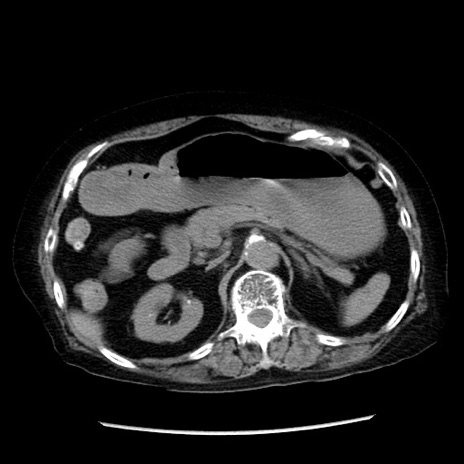

症例14(横断像)

【症例】 90歳代女性

【主訴】 腹痛・嘔吐

【現病歴】今朝から左側腹部痛を認めた。 経過観察していたが、嘔吐を認めたため来院。

【既往歴】 子宮癌術後

【身体所見】 意識清明、BP 127/54mmHg、P 98bpm Sp02 95%(RA)、BT 35.8°C、腹部平坦・軟腸ぜん動音聴取良好、右下腹部圧痛(+) 反跳痛なし

【データ】WBC 9800、CRP 0.46